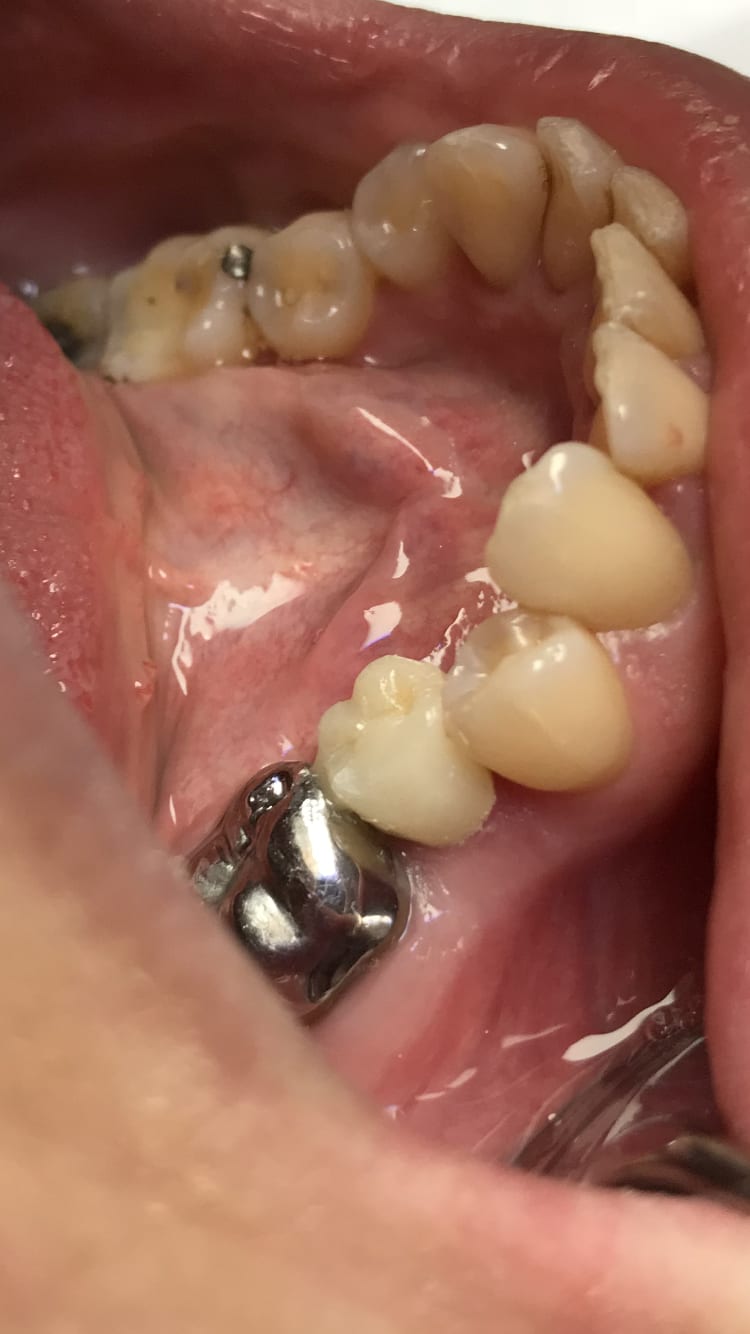

Regardez moi cette petite provisoire sur 45 :-)

S'il t'a demandé dans la foulée de lui refaire sa 46 , tu as eu raison !! Autrement c'est con ;o))

ceci dit , un prov pour une unitaire ça ne sert à pas grand chose .

Allez dis le que ma provisoire est belle. Fais pas ta mijaurée :)))

provisoire réalisée en auto moulage avec Phoenix d'ELSODENT ?

non ,elle n'est pas belle ,elle est très belle :-))

par contre ,on dirait qu'elle est un peu en sur-contour , non ?

Avez vous vu la face occlusale de 36?

La provisoire a un intérêt tout de même :

Il arrive souvent qu’en M ou D on soit bien en sous gingival -> à cause de la carie .

Si on laisse en l’état, et bien la gencive va bourgeonner sur la préparation . Ça ne sera pas une zone qui sera bien nettoyée. Du coup -> petite gingivite dans la zone . Et là vous vous retrouvez comme un con avec une gencive qui a bourgeonné et qui saigne .

La provisoire facilite la prise d’empreinte.

Mais non ma provisoire n’ est pas en sur-contour. Je me suis même cassé le cul à mettre du composite flow A4 dans les sillons pour donner un aspect de « coloration de sillon » . Ça n’a aucun intérêt vous me direz puisque la provisoire est montée en A2 et qu’elle n’a pas la même teinte que les couronnes d’a Coté. Moi je m’arrange presque toujours pour faire une teinte différente de façon à ce que le patient revienne pour sa couronne définitive.

Vulpi tu parles de la 36 ou de la 46 ?

36

Ben quoi ? C’est un peu usé.